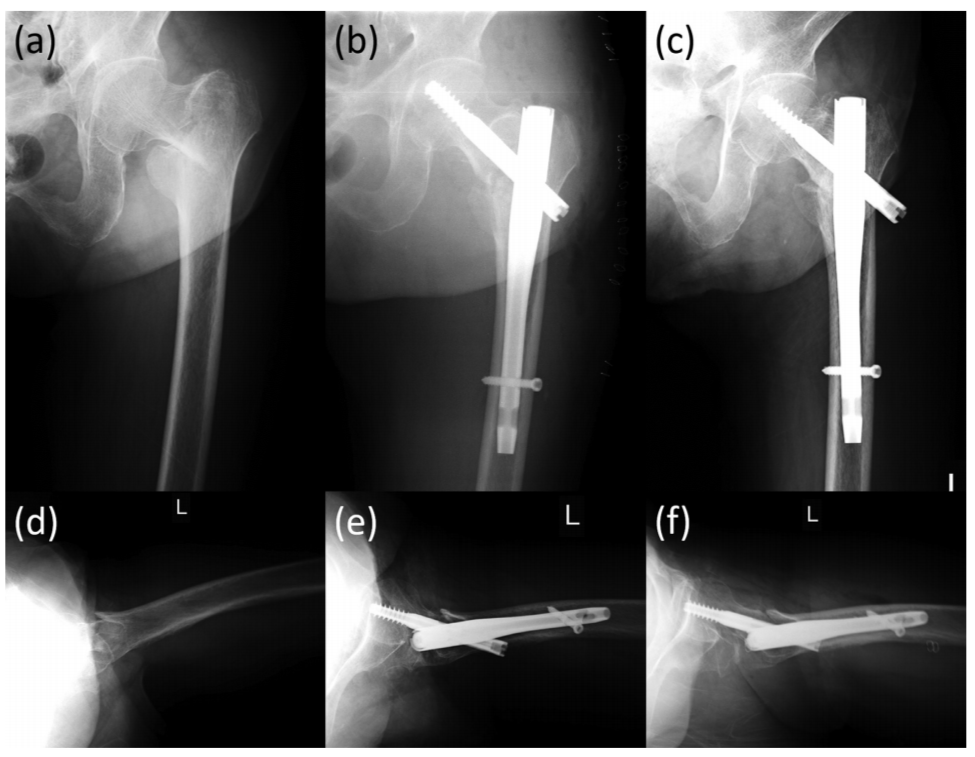

图3 一例92岁股骨粗隆间骨折患者,可见在正位片及侧位片上,骨折均良好显示。